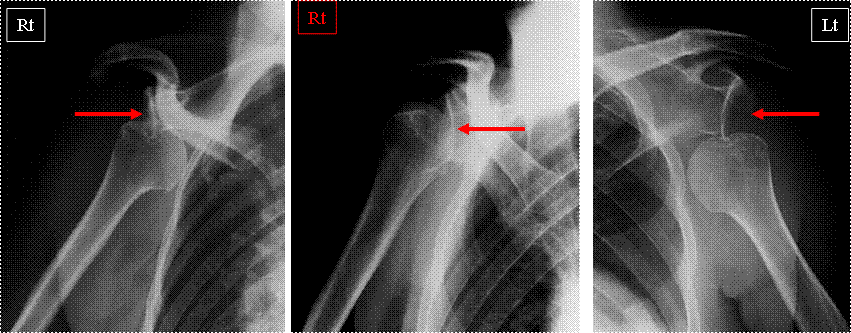

何処に脱臼してますか?

Y view画像なら簡単に理解できます!